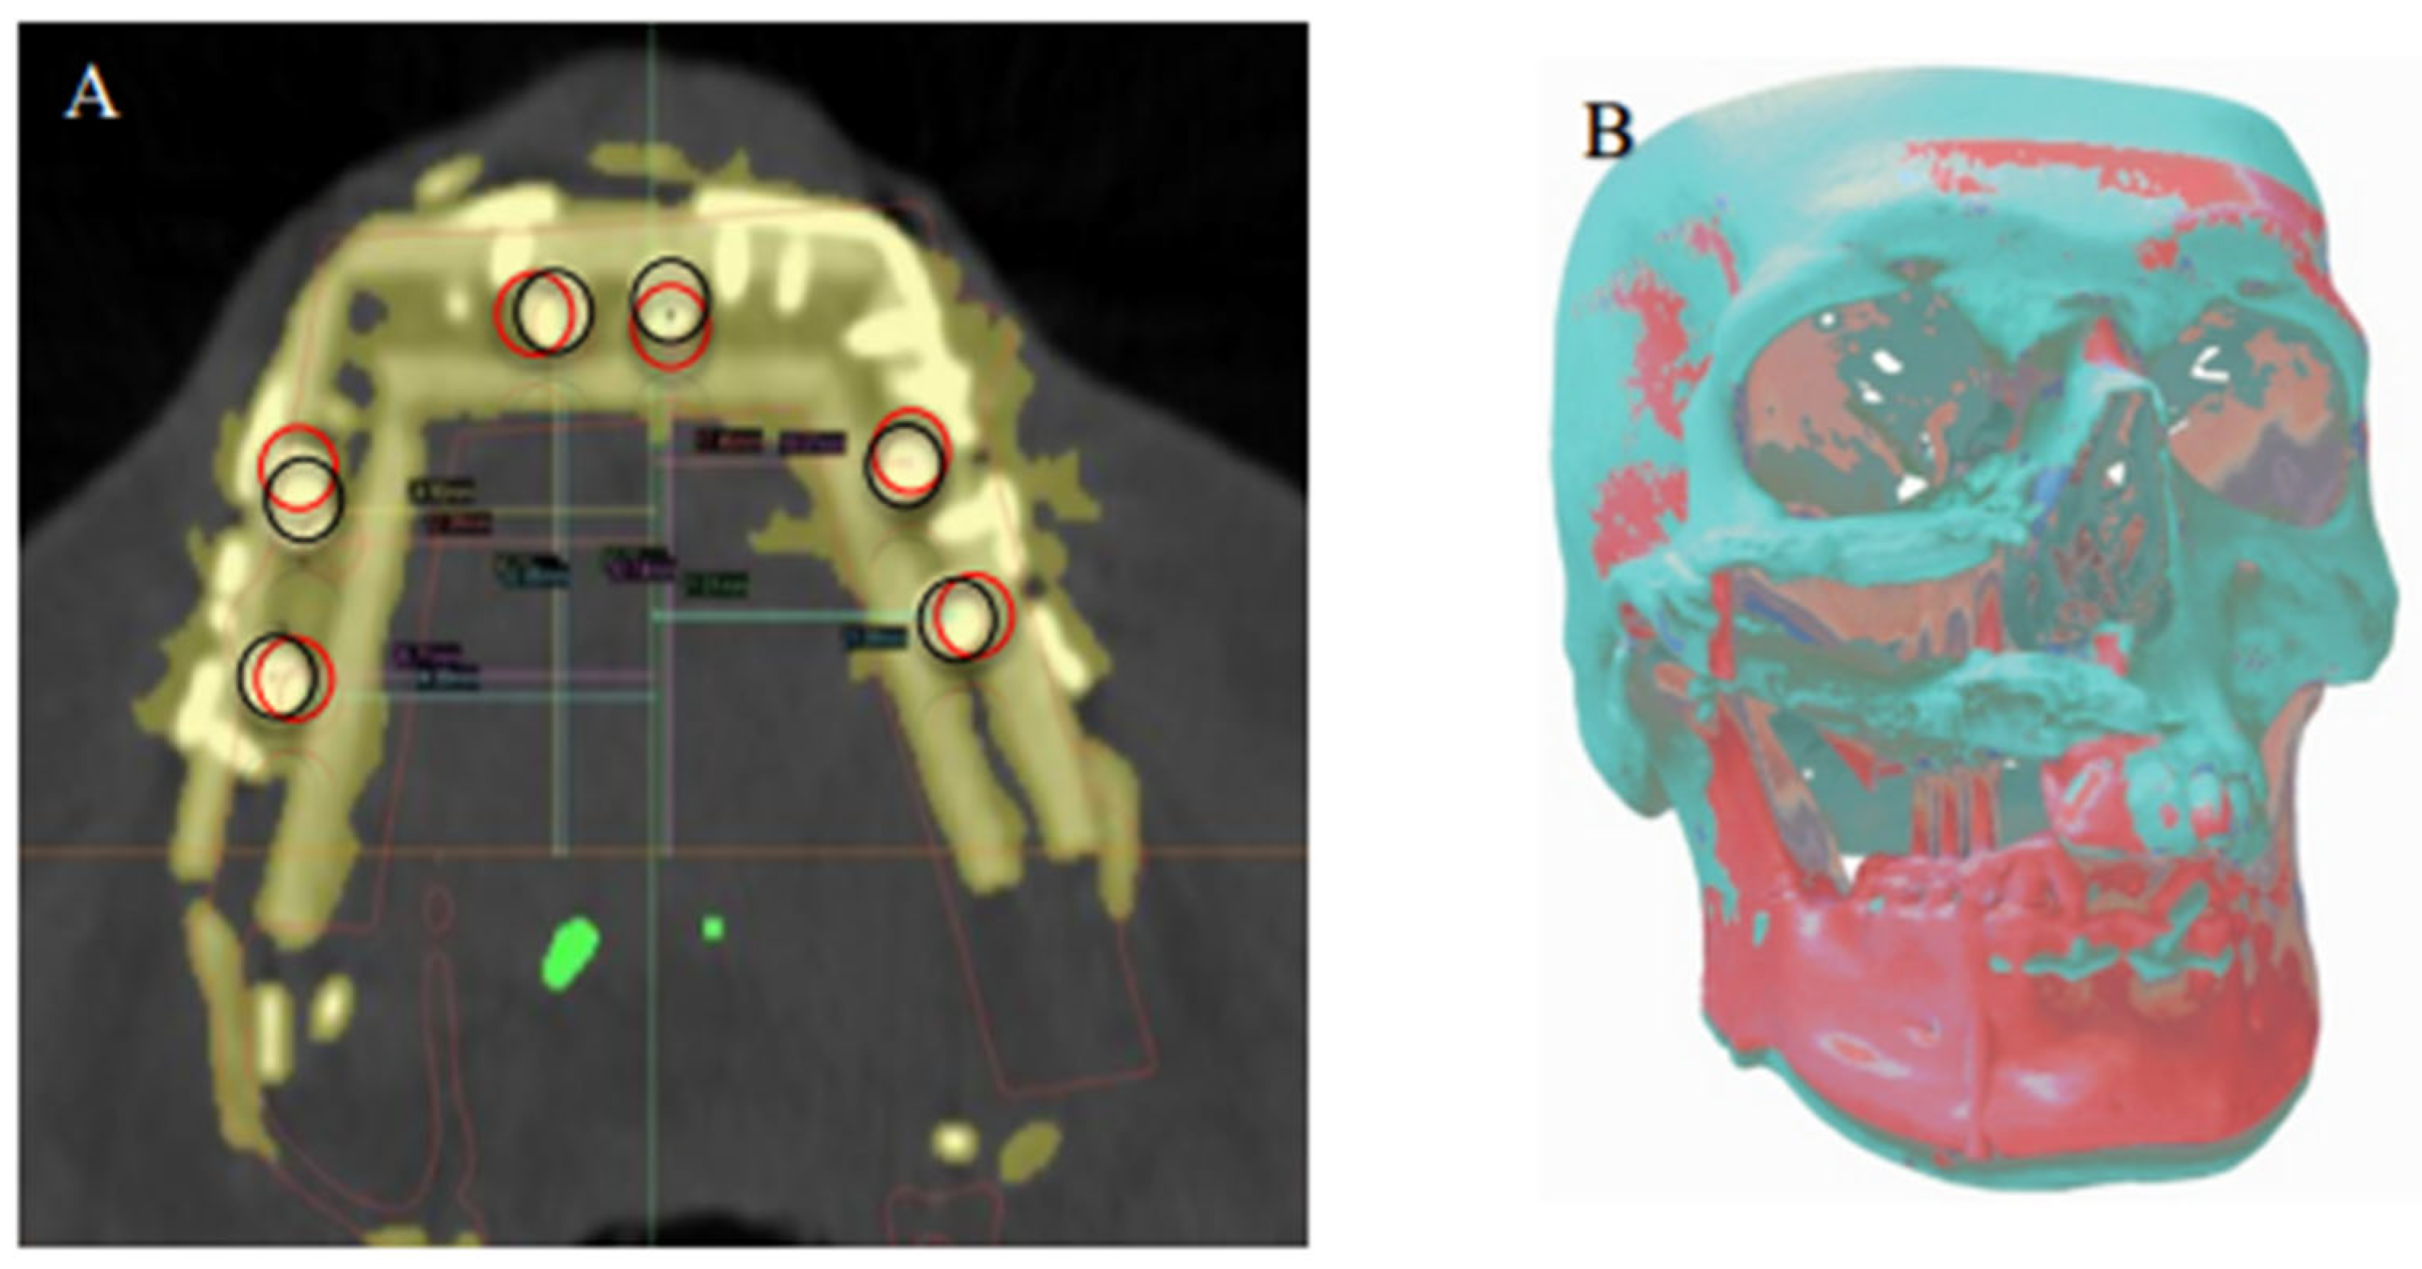

2.6. Data Analysis

The preoperative digital plan, referred to as “planned”, and the scans of the postoperative results, referred to as “actual”, were used for our analysis. Digitally placed spheres (1 mm diameter) were manually positioned in the geometric center of the planned and actual implant positions along the occlusal surface of the fibula. The spheres defined the reference point for measuring implant position. The X, Y, and Z coordinates of each planned and actual implant position were obtained (Figure 5 and Figure 6). The difference in position of the dental implants between the preoperative planned and postoperative actual CT scans was calculated in millimeters.

Figure 7. (A) Superimposition of the planned (black circles) dental implant locations according to virtual reconstruction planning and actual (red circles) implant locations on the postoperative CT. (B) Registration of the preoperative 3D model and the postoperative 3D reconstruction, showing overall deviation from the virtual plan.